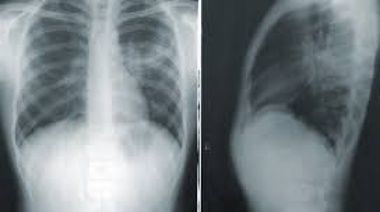

Alarmante aumento de casos en Varela: se reportaron 452 nuevos enfermos de Covid y 2 fallecidos